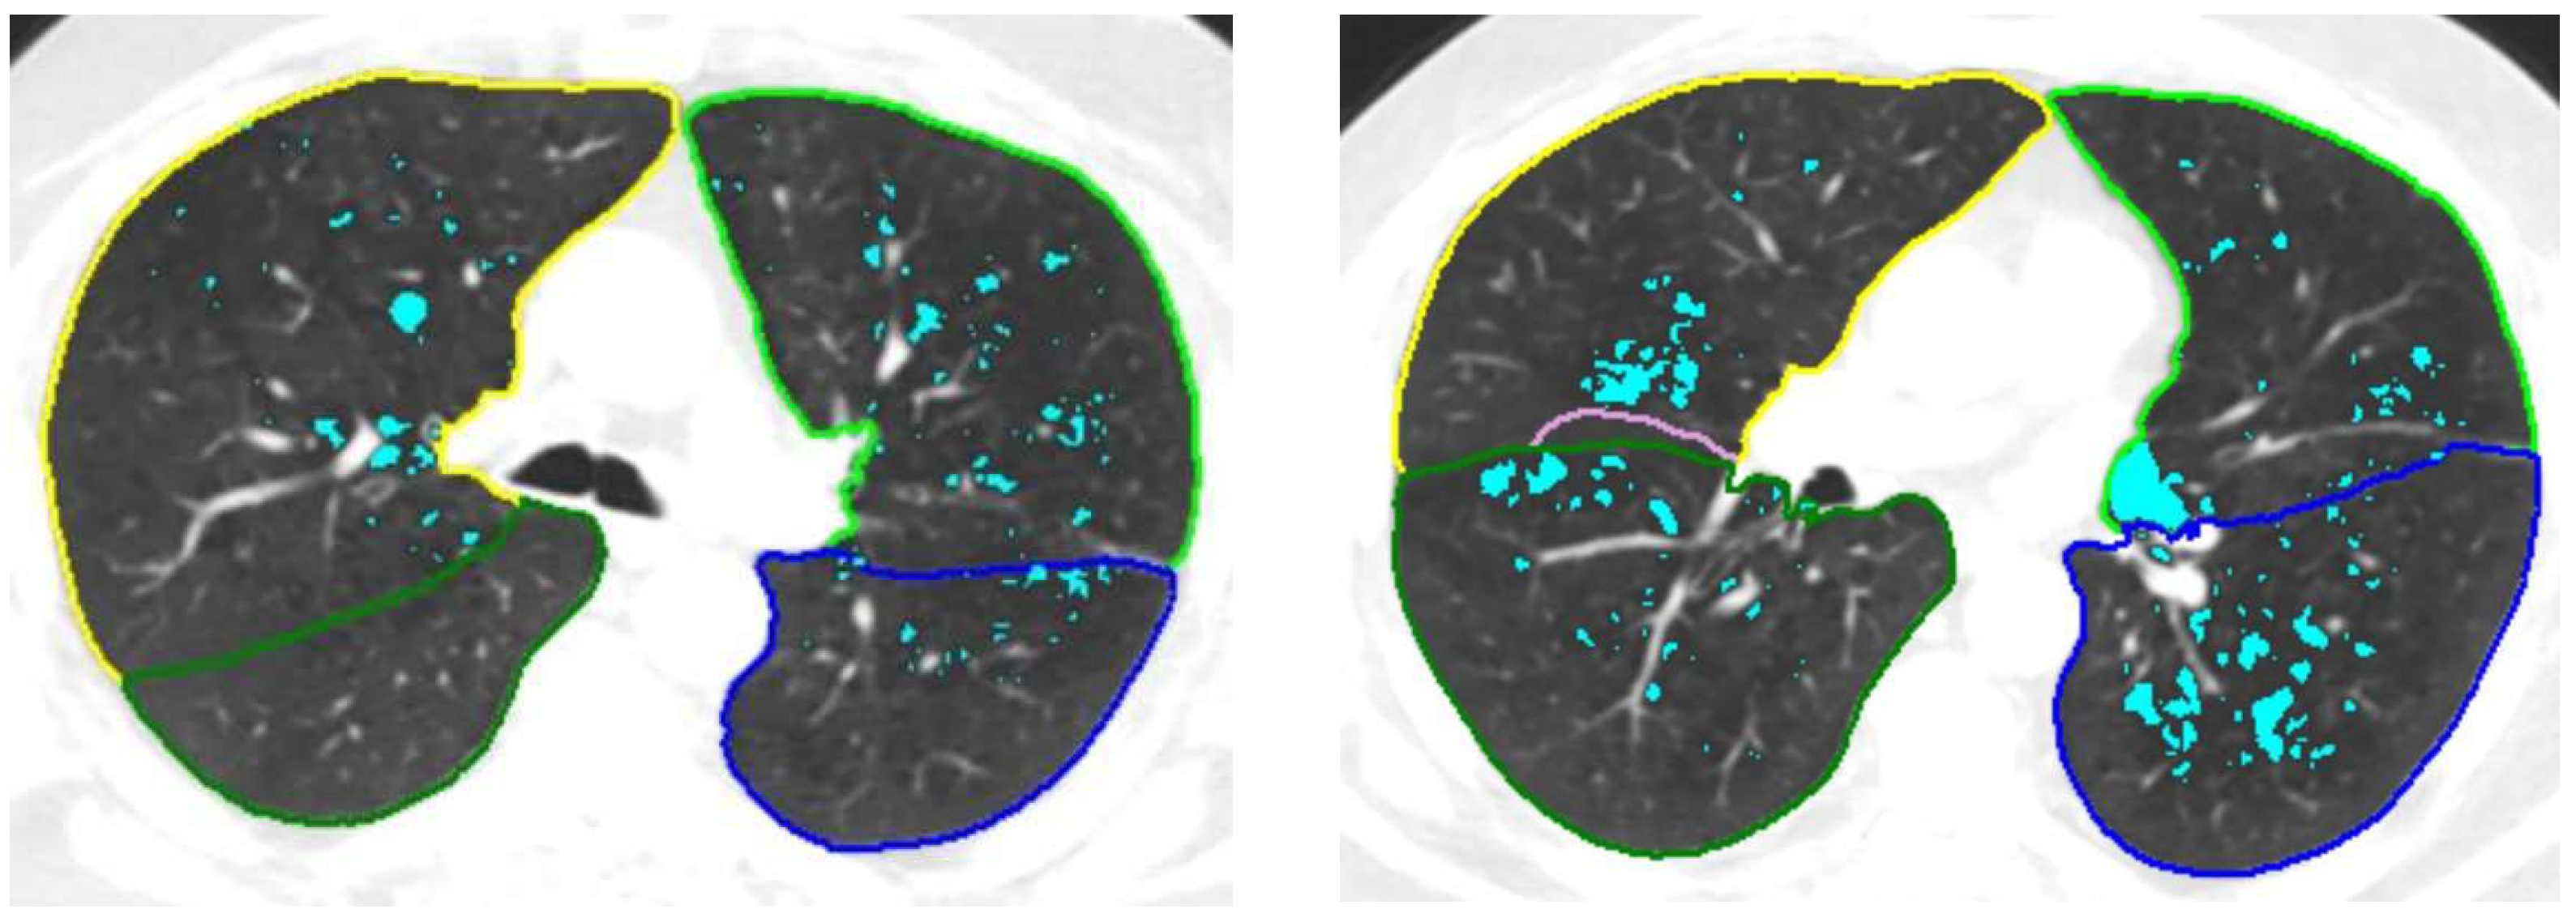

2.1. Lung Segmentation

- Fischer, A.M.; Varga-Szemes, A.; Martin, S.S.; Sperl, J.I.; Sahbaee, P.; Neumann, D.; Gawlitza, J.; Henzler, T.; Johnson, C.M.; Nance, J.W.; et al. Artificial Intelligence-based Fully Automated Per Lobe Segmentation and Emphysema-quantification Based on Chest Computed Tomography Compared with Global Initiative for Chronic Obstructive Lung Disease Severity of Smokers. J. Thorac. Imaging 2020, 35 (Suppl. S1), S28–S34. [Google Scholar] [CrossRef]